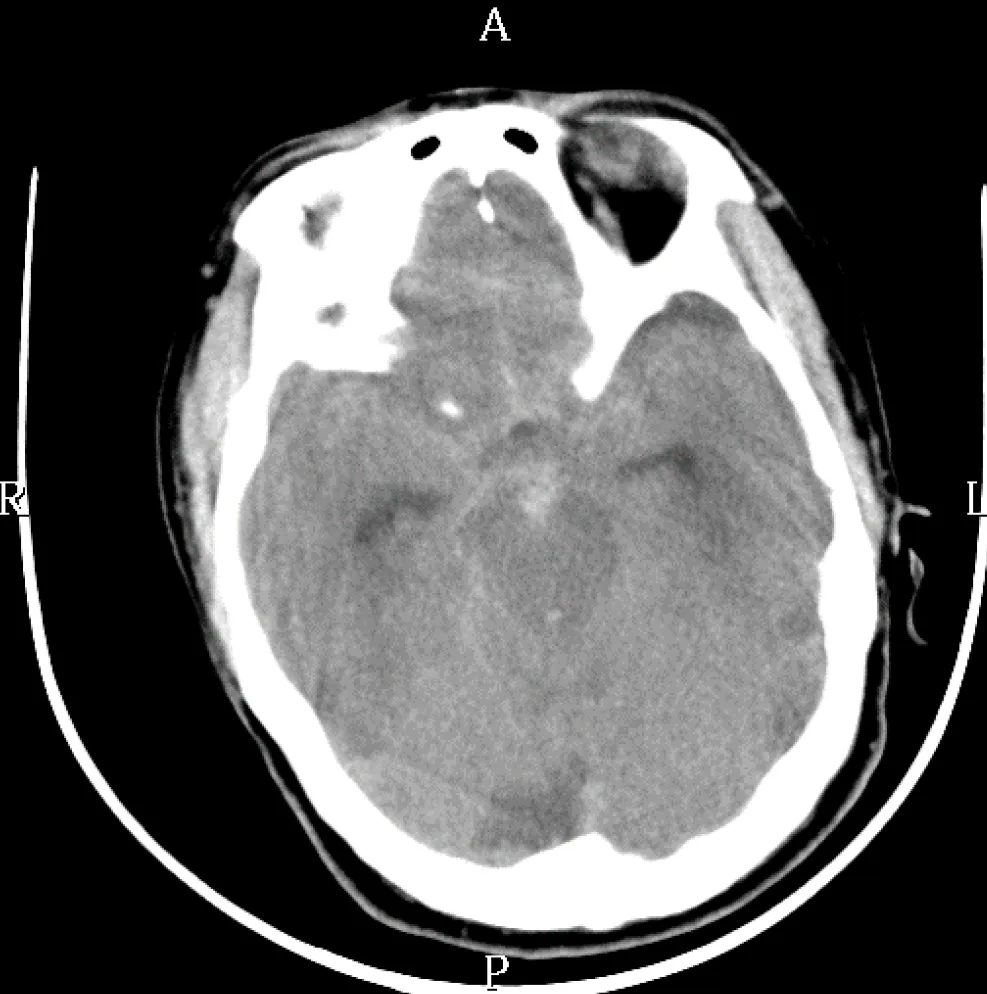

【109-2 醫學(四) 第46題】一位70歲男性病人,有多年高血壓病史,沒有常規藥物控制。早上做晨間運動時,突然失去意識倒地不起,經119轉送急診,腦部電腦斷層掃瞄如下圖,最有可能的診斷為: